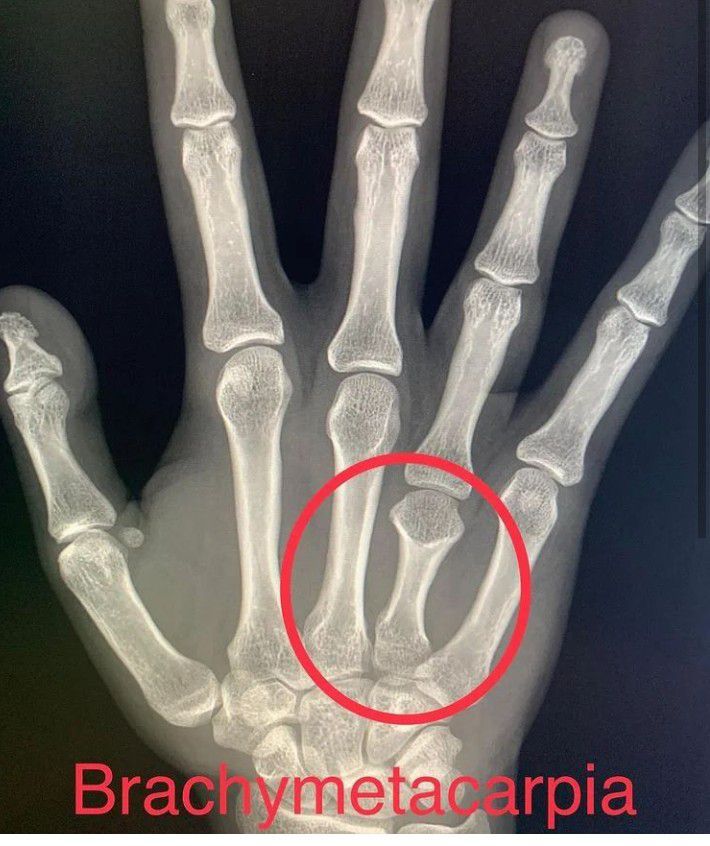

Brachymetacarpia is a rare congenital presentations denoted by shortening of metacarpals in which the deformity usually presents around childhood/early adolescence. It is caused when the growth plate of the metacarpal closes early, resulting in premature stoppage of growth. This can be a congenital condition or can be an acquired deformity following trauma, infection, tumor, radiation, or prior surgery.